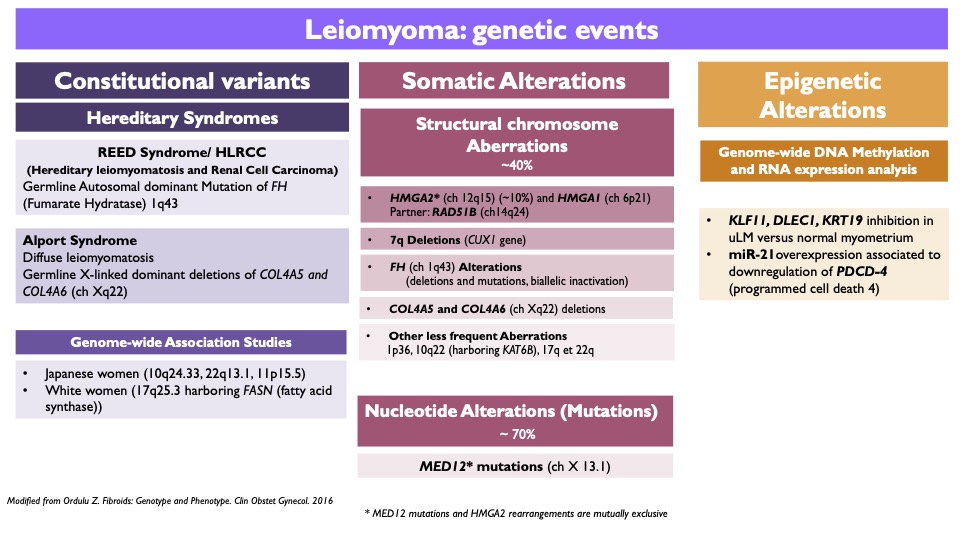

- Several alterations identified (Table 1) (Clin Obstet Gynecol 2016;59:25)

- About 70% of conventional leiomyomas harbor MED12 mutations and nearly 40% HMGA2 / HMGA1 rearrangements, COL4A5 / COL4A6 deletions or FH mutations (Fertil Steril 2014;102:621, Mol Cancer 2017;16:101)

- Other less frequent alterations include 7q22 deletion involving CUX1 gene, 22q deletion with DEPDC5 gene and 1p deletion with NPHP4 gene (Genes Chromosomes Cancer 2013;52:11, Proc Natl Acad Sci U S A 2016;113:1315, N Engl J Med 2013;369:43, Am J Obstet Gynecol 2014;210:572.e1, Cancer Genet Cytogenet 2009;193:54)